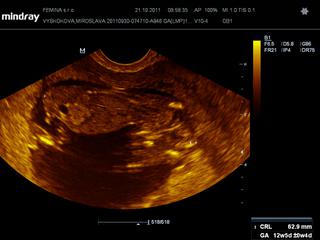

@kaekole zatial som bola len na tom vaginalnom sone. dnes mi robil, dnes som v 12+1, potom mi robil pred tyzdnom a potom este v 9+1.

ale dnes mi meral aj NT - ako si mi raz pisala, dokladne malicke prezrel + este mi povedal, ze ak chcem mat 100% istotu, aby som isla do Martina k jednemu specialistovi - MUDr. Frantisek Grochal

@lenkalela ja som citala, ze do 3 mm je to uplne v poriadku, tak sa nicoho neboj

tu je foto z dnesnej poradne 🙂